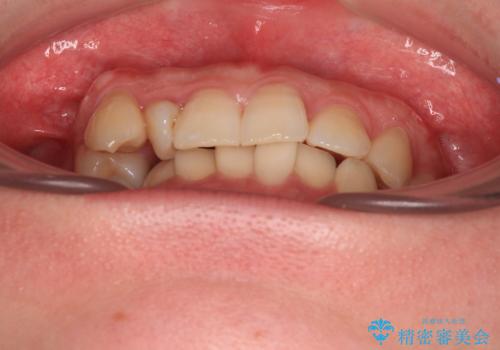

捻転の強い前歯 ワイヤー装置での非抜歯矯正

- 前歯のデコボコ、特に90度捻れている上顎前歯を気にして来院された患者様です。

マウスピースでもワイヤーでも対応可能でしたら、捻転が非常に強いことから、患者様と相談の上ワイヤー装置にて矯正治療を行うこととしました。

捻転を解消する際に、歯列全体が前方に突出して出っ歯の仕上がりとなることが懸念されたため、補助装置を用いて上顎歯列全体を後方に移動する力をかけることとしました。